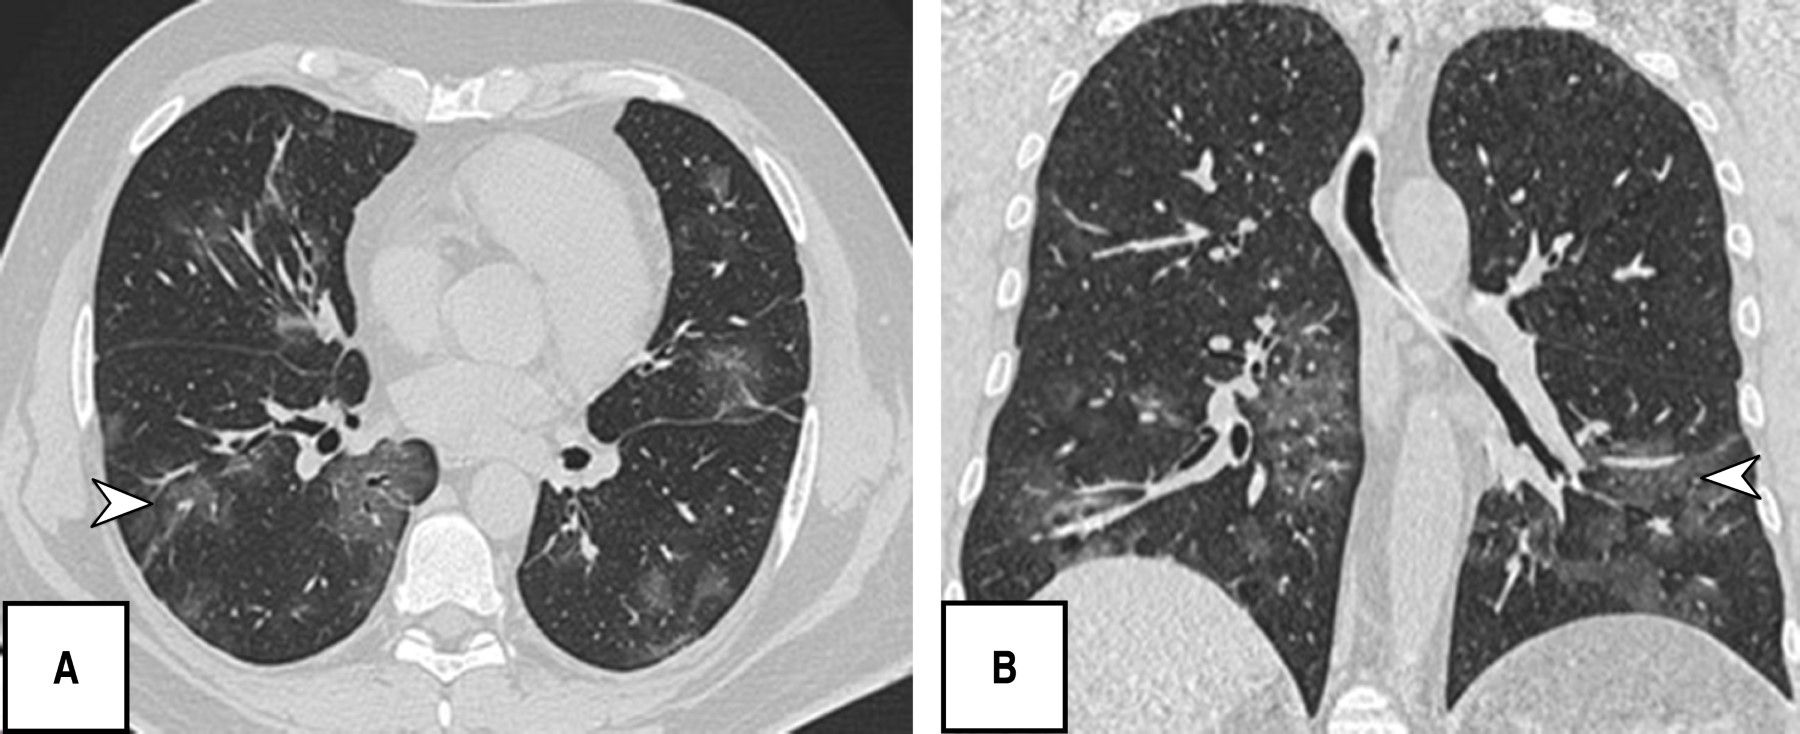

During the tomographic evaluation, the most frequent pulmonary patterns were: cobblestone pattern (120 [80.5%]), pleuroparenchymal bands (118 [79.2%]) and ground glass pattern (110 [73.8%]), reticular pattern (82 [55%]), and in lower percentage vascular dilatation (56 [37.6%]) and consolidated pattern (52 [34.9%]) (Figures 1, 2, 3 and 4).

Regarding the phases found, the resorption phase was observed most frequently (69 [46.3%]) followed by the peak phase (40 [26.8%]) (Table 2).

It is noteworthy that most of the patients in this research presented in a chronic/advanced phase of the disease, finding as predominant patterns the cobblestone (120/149; 80.5%), pleuroparenchymal bands (118/149; 79.5%) and in third place ground-glass pattern (110/149; 73. 8%), without identifying any case with findings of atoll, pneumothorax or twinning tree, other studies do report ground glass opacities as the predominant finding followed by the consolidation pattern and in this regard pleural effusion, pericardial effusion, lymphadenopathy, cavitation, the reverse halo or atoll sign and pneumothorax are rare, but can be observed with the progression of the disease.19-21

Soriano et al. reported that the presence of ground-glass opacities, reticular pattern, cobblestone pattern, subpleural lines, pleural thickening and fibrosis were more frequently found in the intermediate/progressive phase, especially in the advanced phase; similarly we observed a significant correlation (Pearson's index of 0.65) between the predominant pattern and the progressive phase of the disease.23 The CT scores of the progressive stage group were significantly higher than those of the early stage group; however, in this study there was no statistical significance between CT pattern and severity score.